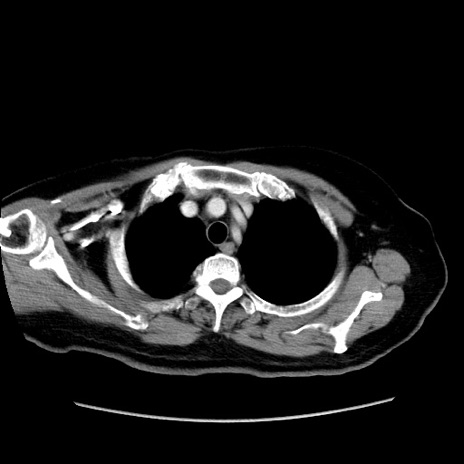

症例19(横断像)

【症例】80歳代女性

【主訴】下腹部痛

【現病歴】約8時間前より下腹部痛の出現あり、救急外来受診。

【既往歴】両側付属器切除

【身体所見】意識清明、下腹部正中に手術痕あり、その部位に一致して圧痛と反跳痛あり。腸蠕動音は亢進。

【データ】WBC 9300、CRP 0.15